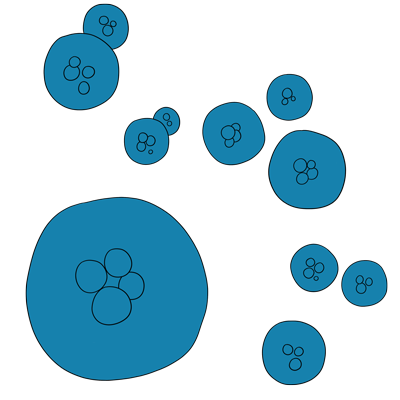

Stem cells come in different types and are derived from various sources. The stem cells used in SCI research are either pluripotent or multipotent, in the main. Pluripotent cells are capable of changing into many specialised types of cell via differentiation. Multipotent cells are also able to differentiate, but the end cell types are more limited.

- Embryonic – pluripotent and derived from the inner cell mass of the blastocyst (a 5-7 day old cluster of cells in early embryonic development)

Stem cells can be categorised by their ability to differentiate. Pluripotent stem cells can form any of over 200 different cell types found in the body.